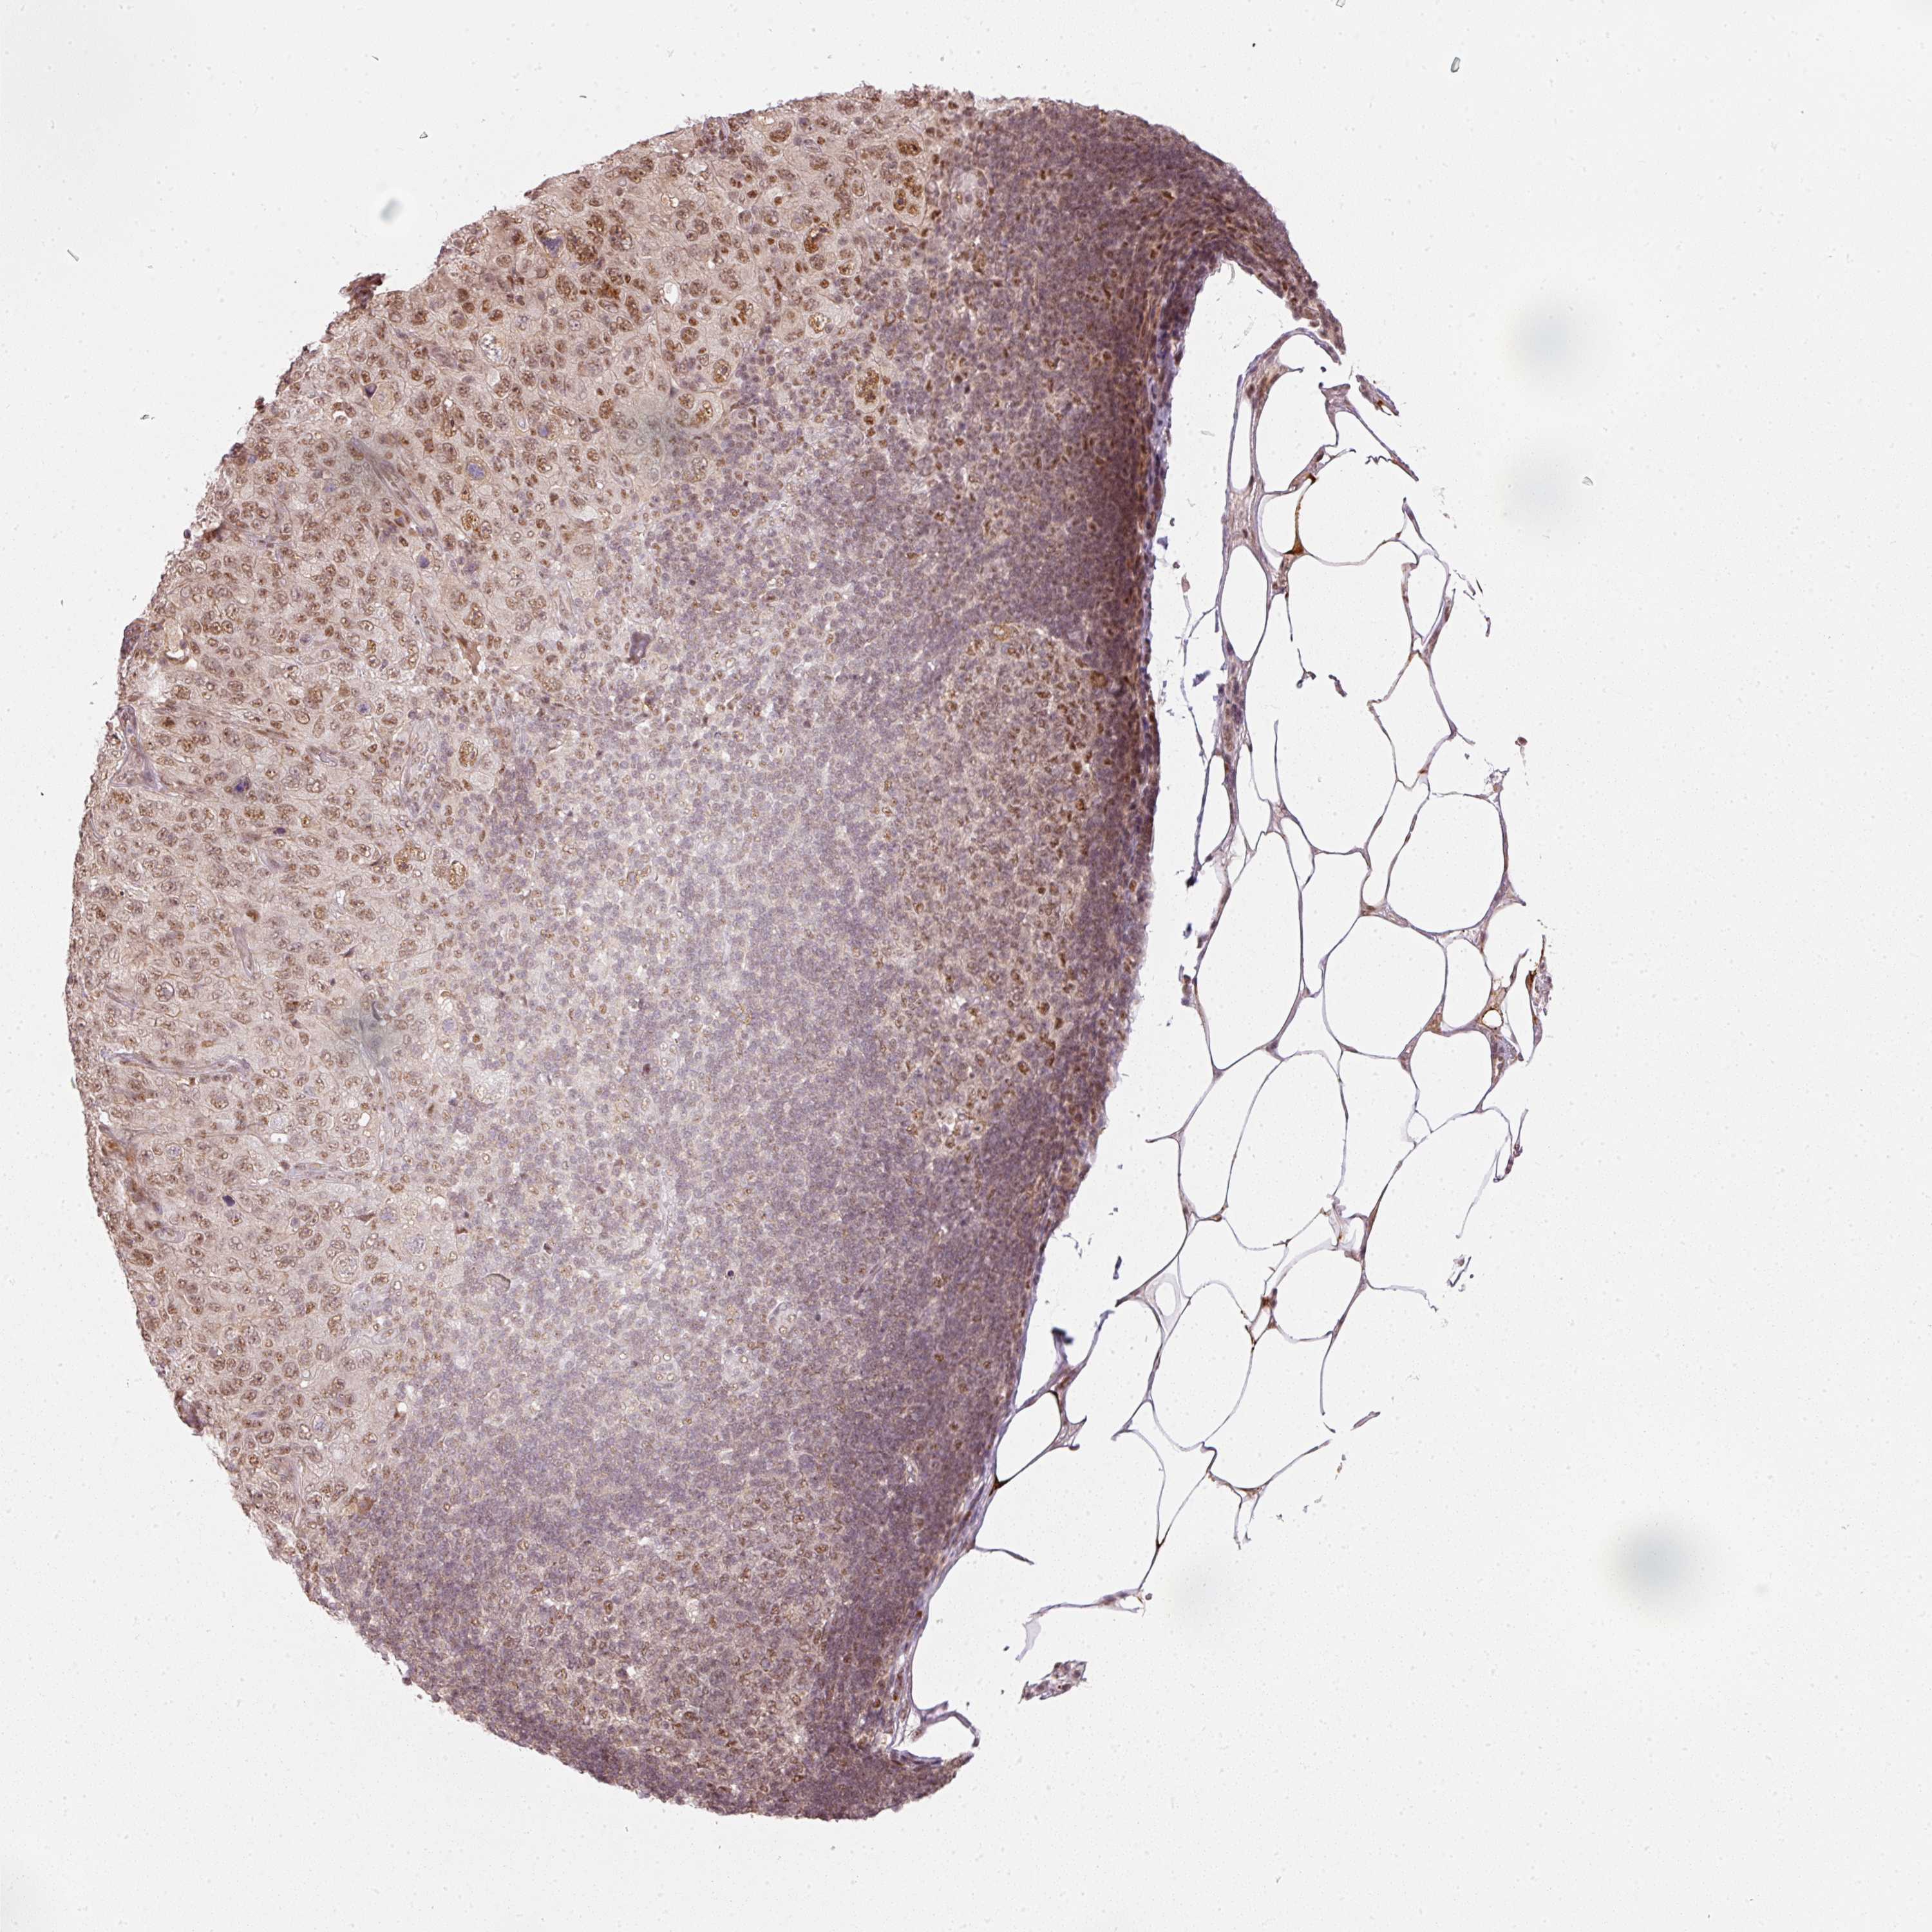

PANCREATIC CANCER - Protein expressioni

A mouse-over function shows sample information and annotation data. Click on an image to view it in a full screen mode. Samples can be filtered based on level of antibody staining by selecting one or several of the following categories: high, medium, low and not detected. The assay and annotation is described here.

Note that samples used for immunohistochemistry by the Human Protein Atlas do not correspond to samples in the TCGA dataset.

Antibody stainingi

Antibody staining in the annotated cell types in the current human tissue is reported as not detected, low, medium, or high, based on conventional immunohistochemistry profiling in selected tissues. This score is based on the combination of the staining intensity and fraction of stained cells.

Each image is clickable and will lead to virtual microscopy that enables deeper exploration of all samples and also displays staining intensity scores, fraction scores and subcellular localization as well as patient and tissue information for each sample.

Antibody HPA052953

Staining

High

Medium

Low

Not detected

Intensity

Strong

Moderate

Weak

Negative

Quantity

>75%

75%-25%

<25%

None

Location

Nuclear

Cytoplasmic/membranous

Cytoplasmic/membranous,nuclear

Adenocarcinoma, NOS